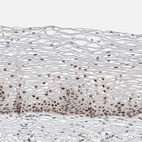

Immunohistochemical staining of human endometrium shows moderate to strong nuclear positivity in glandular cells.